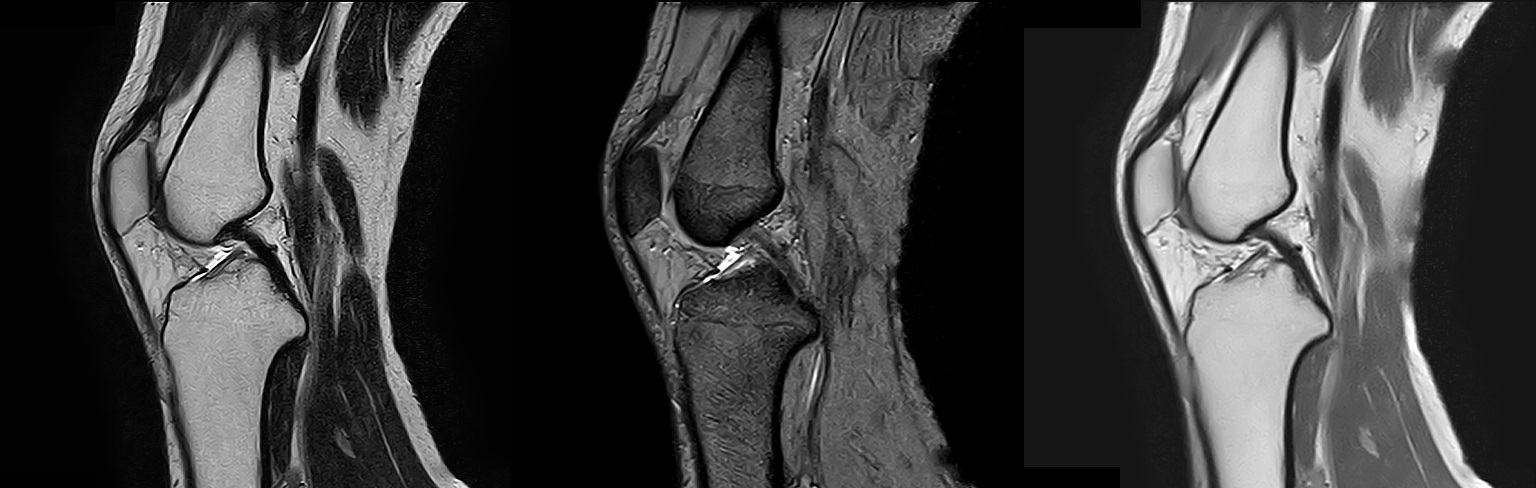

T1強調像 / T2強調像 / FLAIR像 / T2*強調像

頭部

T2強調像 / T2*強調像 / プロトン密度強調像